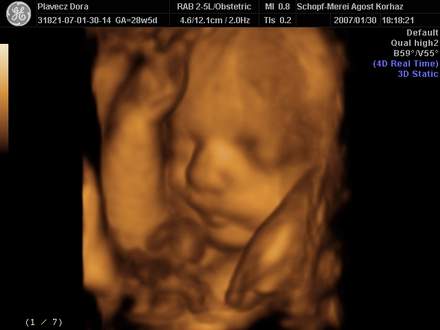

Dorki,

nem tudsz feltenni 3D-s képet?És milyen most,hogy fiús érzésed van?Mivel másabb,mint a Nikivel?